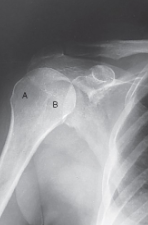

label the anatomy accordingly A-G, the projection/part, and rotation if applicable

head of humerus, greater tubercle, intertubercular sulcus, lesser tubercle, anatomic neck, surgical neck, body

AP shoulder — external rotation